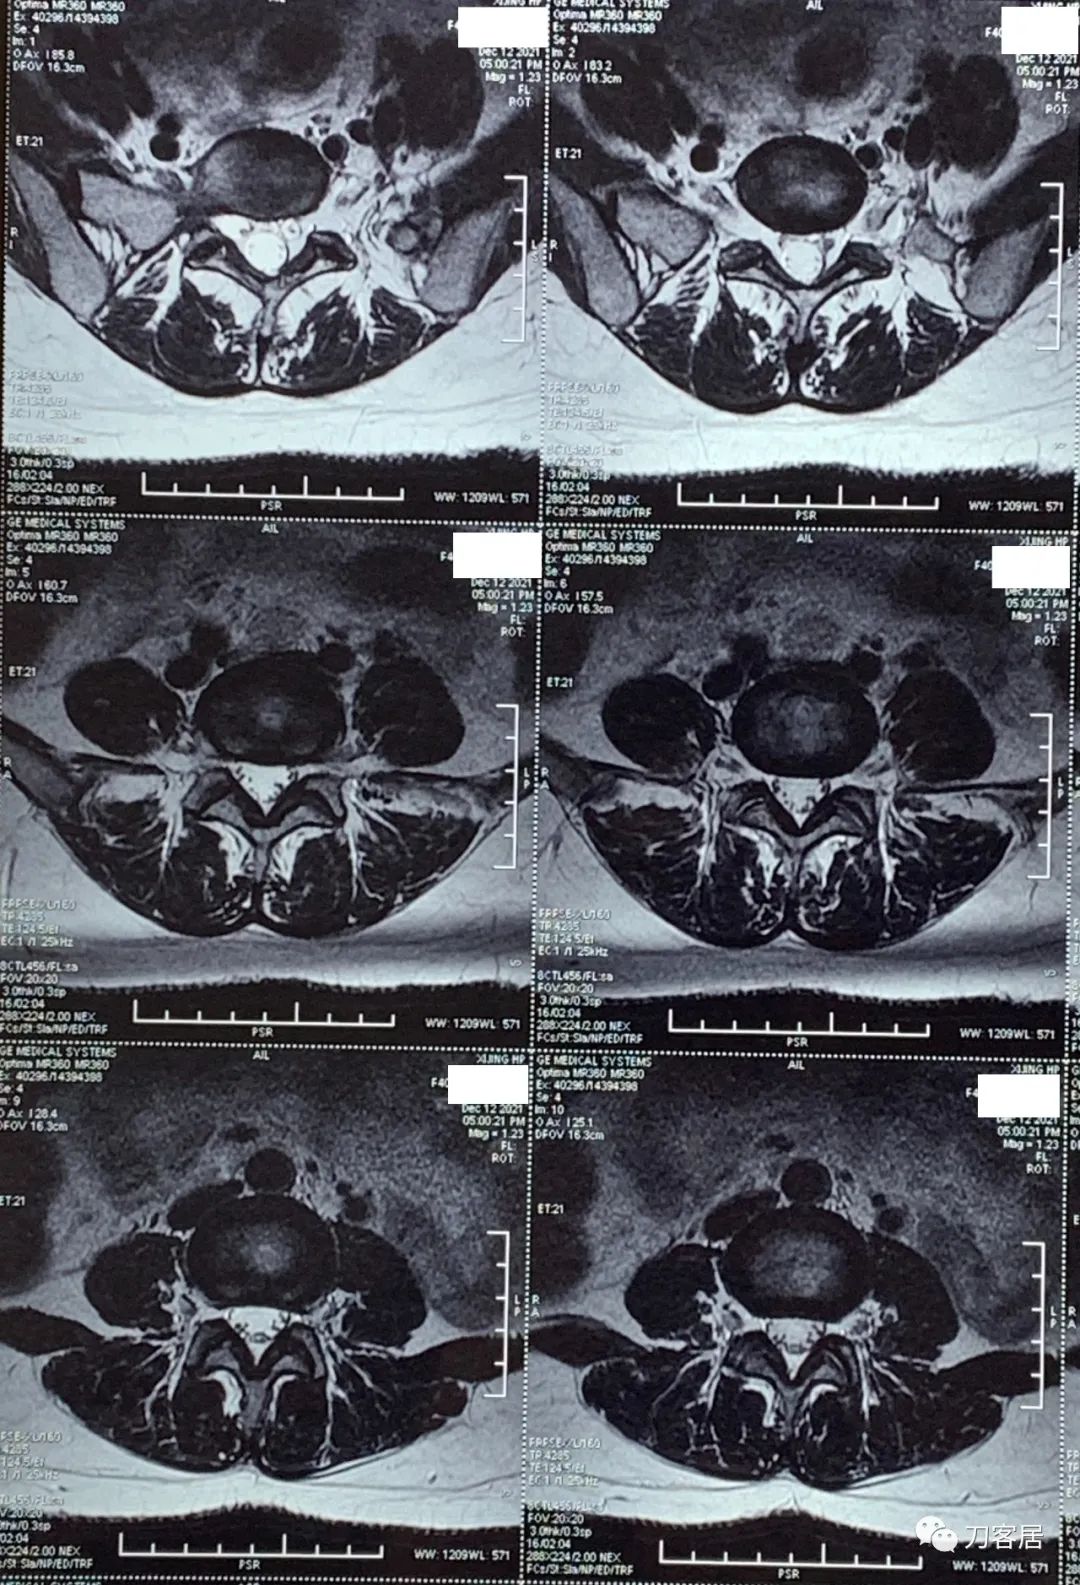

自带腰椎MRI检查未见异常。腰椎X线片提示左侧腰5横突肥大。自带外院骨密度检查结果正常。

20211212西京医院腰椎MRI.